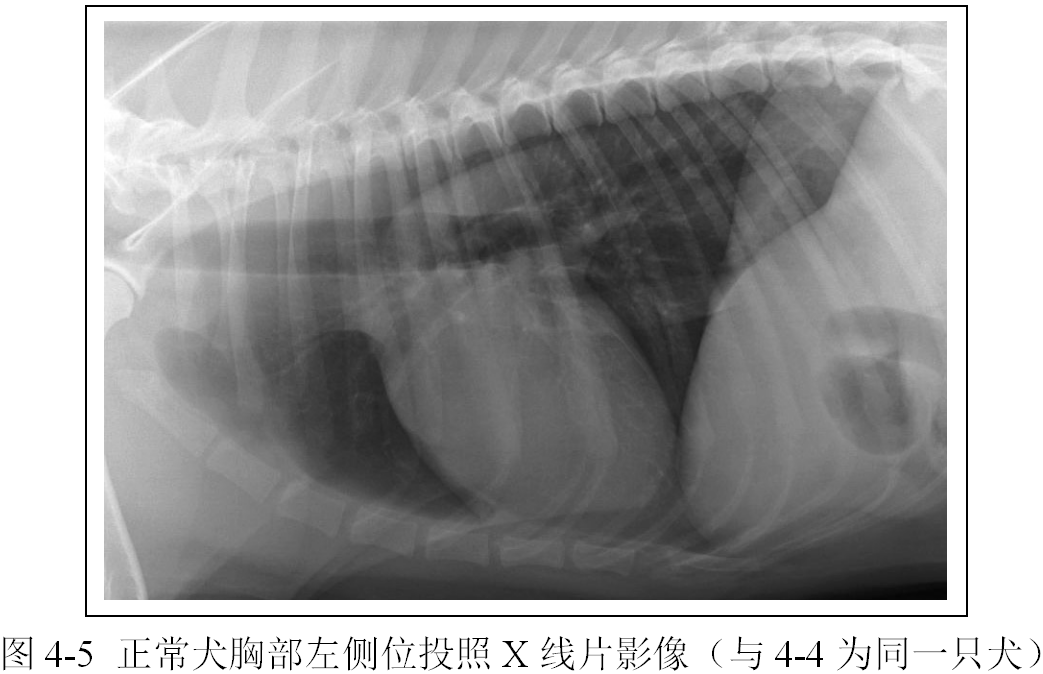

(2)识别胸椎、肋骨、胸骨、横膈外围结构影像(图4-4、4-5、4-6、4-7,注意观片灯评估X线影像时X线片的正确放置)。

(3)识别心脏、大血管、肺脏、气管、支气管影像(图4-4、4-5、4-6、4-7)。

(4)区分右侧位和左侧位以及腹背位和背腹位投照的明显区别(图4-4、4-5、4-6、4-7)。